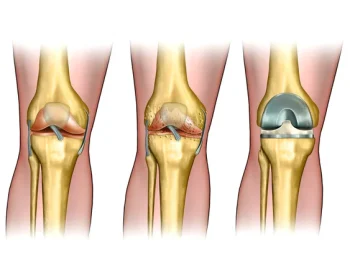

Total knee replacement is a surgical procedure that replaces the entire knee joint, alleviating pain and improving function for advanced arthritis or severe damage.

Patellar resurfacing is a procedure that smooths and resurfaces the underside of the kneecap, reducing pain and improving movement in cases of cartilage damage.